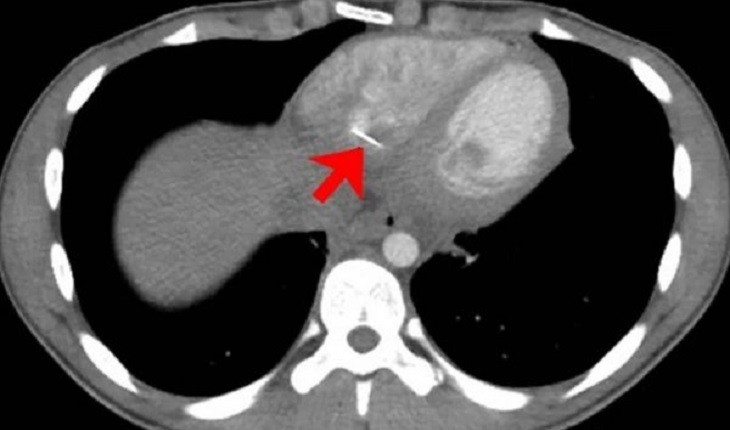

O caso foi registrado nos Estados Unidos e publicado no científico The Journal of Emergency Medicine.